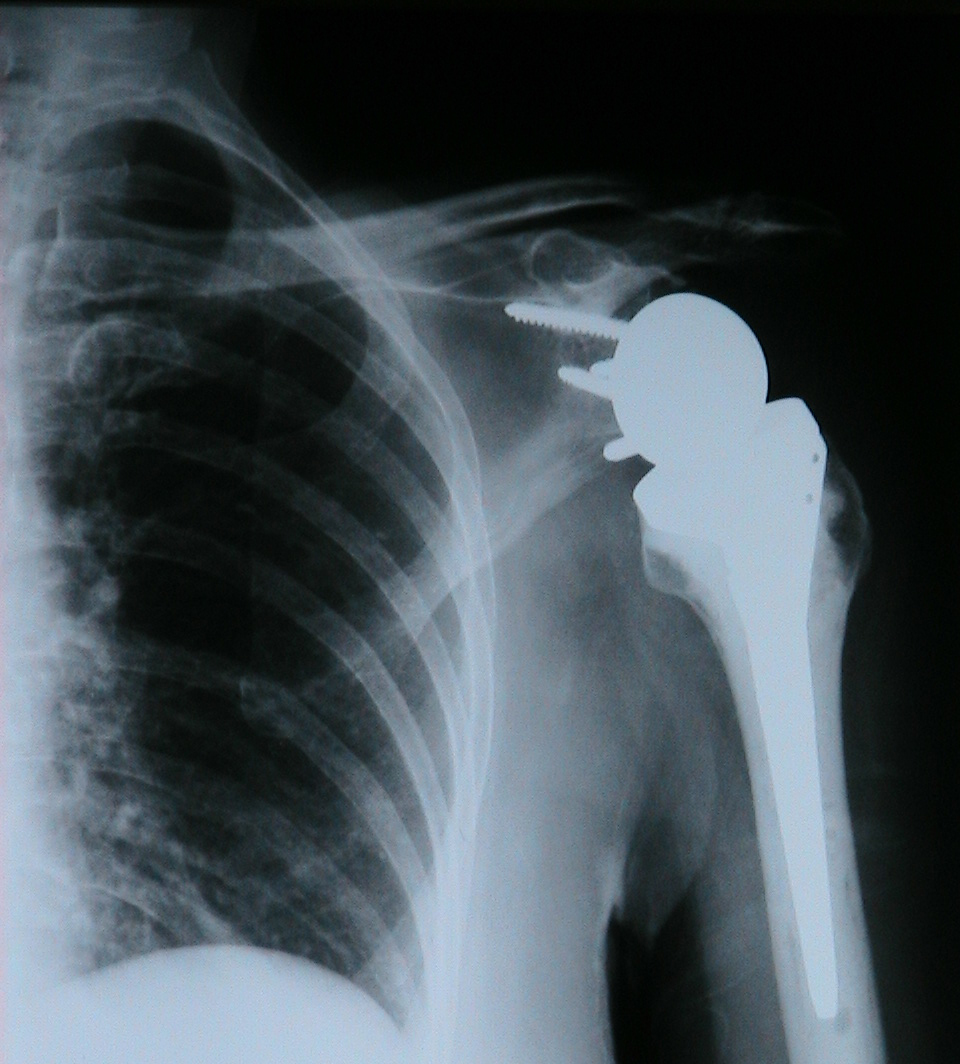

ΕΠΑΝΟΡΘΩΤΙΚΗ ΧΕΙΡΟΥΡΓΙΚΗ - ΩΜΟΣ